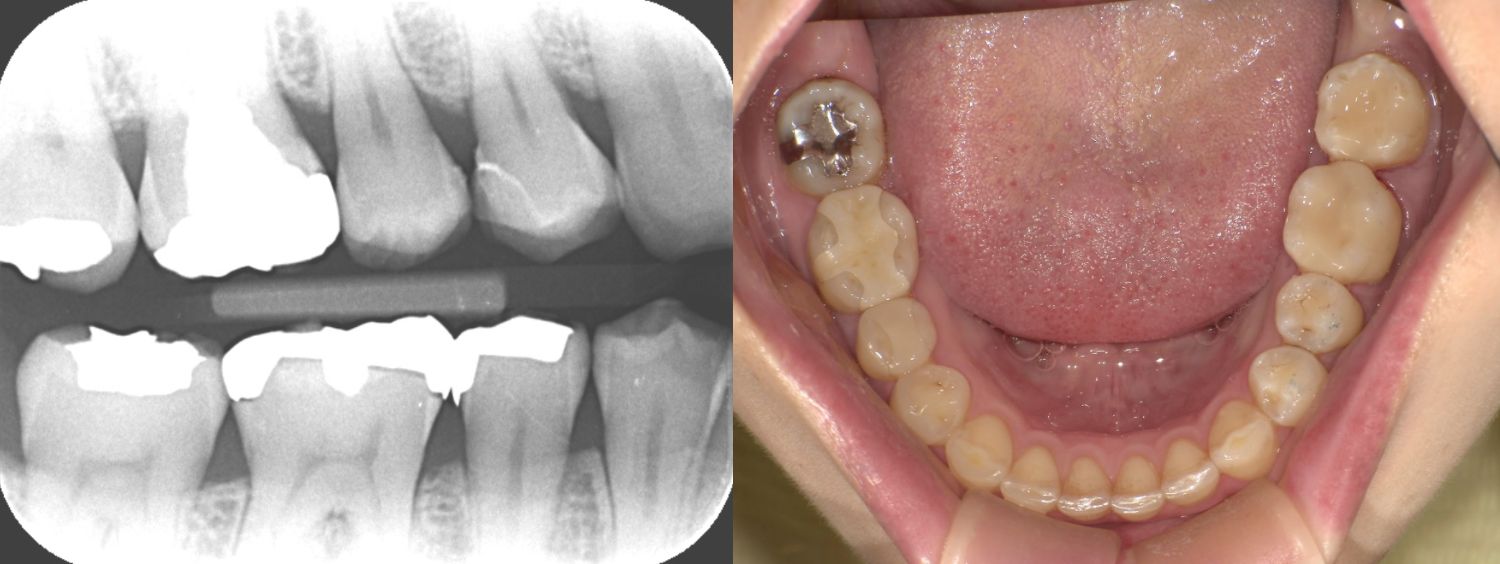

2025/04/22 セレック

SY1443様

通院時年齢 47歳

性別 男性

通院目的 銀歯を白くしたい

診断 銀歯による不適からきたう蝕

処置内容 (または主訴) セレック治療

通院期間 1歯1日(しっかりとした健康な歯肉の状態にまずはしてからの治療になります)

費用

セレック治療 1歯77,000円

リスク・副作用

銀歯直下によるう蝕が広範囲に広がっていた際には神経処置になることがありその場合には1日でセレックに置き換える治療から神経を保存する治療もしくは神経を除く処置に移行する場合があります。 研磨や調整が難しく定期的なメンテナンスが必要になることがある、自由診療となるため費用が高額となる